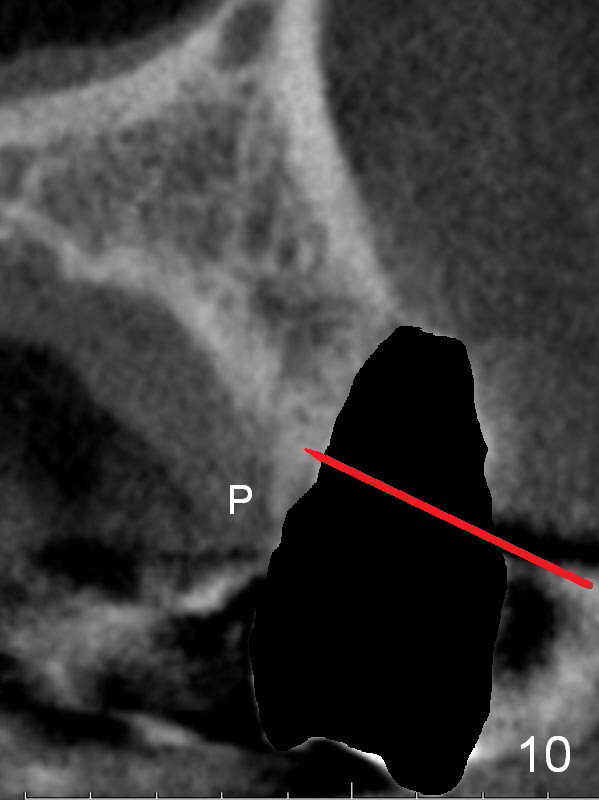

After extraction, the bottom of the socket must be oblique (Fig.9 arrowheads). As usual, osteotomy is initially at the junction of palatal (Fig.10 P) 1/3 and middle 1/3 perpendicular to the plate. Once the drill gets engaged, the trajectory is to be changed (Fig.11 curved arrow) so that the apical end of the osteotomy (red line) is as close to the buccal plate (B) as possible. The purpose is to keep the palatal end of the osteotomy as palatal as possible. In spite of the effort, an angled abutment is expected, as large as 20 degree (Fig.8 purple angle).